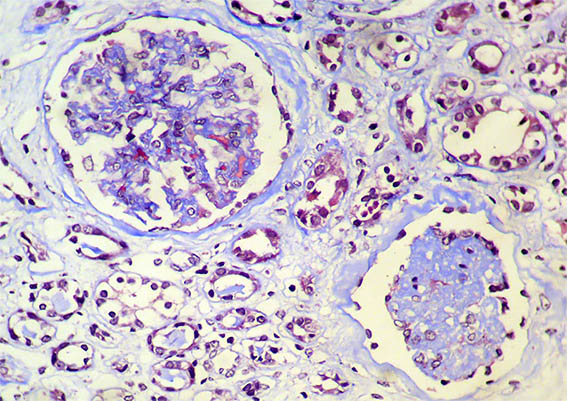

Figure 2. Masson's trichrome stain, X200.